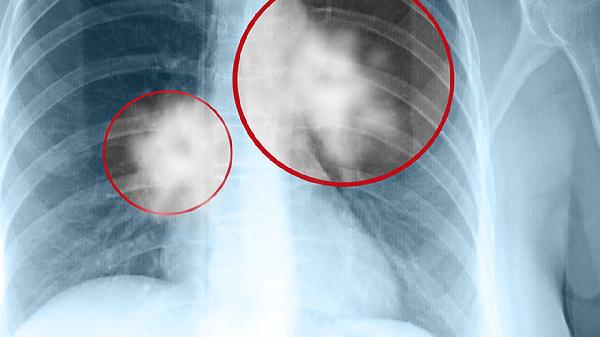

单项轻度升高常见于炎症、良性肿瘤等非恶性情况,需结合临床表现和其他检查综合判断。例如长期吸烟者癌胚抗原轻度升高可能仅反映肺部慢性炎症。但持续2-3个月连续复查仍进行性升高时,需警惕早期肺癌可能。此时需配合胸部CT明确诊断。肝脏良性病变引起的甲胎蛋白升高一般不超过参考值3倍,若超过10倍则高度怀疑肝癌。

3项以上同时显著异常时恶性肿瘤概率大幅增加。例如胃癌患者常出现癌胚抗原、糖类抗原724和糖类抗原199联合升高。卵巢癌常见糖类抗原125超过正常值20倍且伴随糖类抗原153异常。多发性骨髓瘤可能导致β2微球蛋白与神经元特异性烯醇化酶同步超标。此时需根据重点异常指标对应器官,针对性进行胃肠镜、超声、增强CT或PET-CT检查。

某些极端情况如6项全部超标需考虑晚期肿瘤全身转移。以胰腺癌为例,终末期可表现为癌胚抗原、糖类抗原199、糖类抗原724等多项标志物同时超过正常值50倍以上。但需注意部分非肿瘤性疾病如肝硬化急性期、系统性红斑狼疮活动期也可能造成多指标假阳性。无论指标异常数量与程度如何,最终确诊必须依靠病理组织活检。